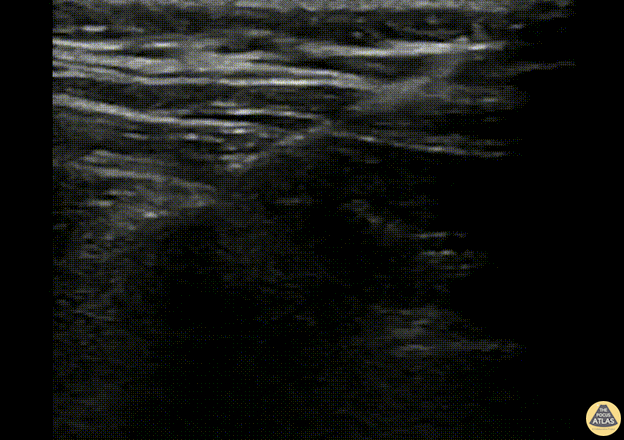

A 43-year-old female presented to the ED with four weeks of ongoing R sided costovertebral angle and anterior chest wall discomfort, previously having been treated for pyelonephritis at the onset of her pain. Given her nonspecific symptoms that had been refractory to standard management, a right sided erector spinae block was offered for analgesia. The needle can be seen approaching the T6 transverse process (the approximate site of her pain) from cephalad. The erector spinae muscle is lifted off the transverse process with good spread in the fascial plane demonstrated in the subsequent images. 30 cc of 0.33% bupivacaine with 10 mg of dexamethasone was used. The patient had moderate pain relief. Dr. Fred Milgrim, Ultrasound Fellow, Denver Health Emergency Medicine